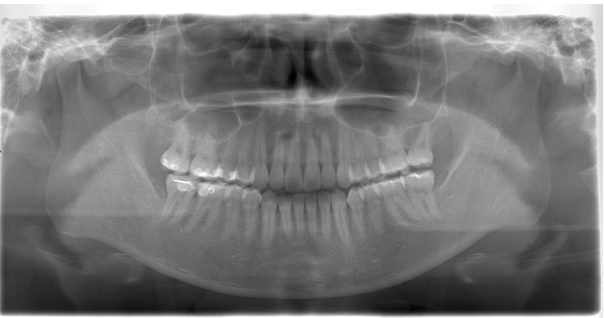

After

| 通院時の年齢 | 25歳 |

| 性別 | 女性 |

| 通院回数 | 2.5年 |

| 通院目的 | 歯列矯正 |

| 処置内容 | インビザラインによるマウスピース矯正 |

| 費用 | 80万 |

| デメリット・注意点 | 患者の協力に起因する 今回親知らずのの萌出も左上では必要のため出てこない場合は更に必要が2万加算される可能性があった |